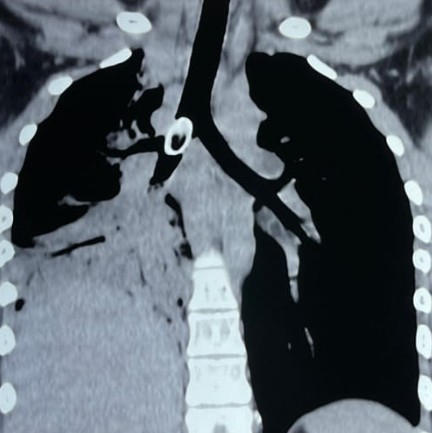

স্থানীয় স্বাস্থ্যকেন্দ্রে প্রাথমিক চিকিৎসা ও এক্স-রে করা হলেও অবস্থার উন্নতি হয়নি। পরে পরিস্থিতি জটিল হওয়ায় তাকে কলকাতায় রেফার করা হয়। এনআরএস-এ ভর্তির পর চিকিৎসকেরা বুকে সিটি স্ক্যান (থোরাক্স) করান। তাতে দেখা যায়, ডান দিকের প্রধান ব্রঙ্কাসের মুখে একটি বড় বস্তু আটকে রয়েছে। ফলে ডান ফুসফুসে বায়ু চলাচল প্রায় সম্পূর্ণ বন্ধ হয়ে গিয়েছিল।

পরিস্থিতির গুরুত্ব বুঝে দ্রুত ফাইবার-অপটিক ব্রঙ্কোস্কোপির সিদ্ধান্ত নেওয়া হয়। পালমোনারি মেডিসিন বিভাগের বিশেষজ্ঞ দল অত্যাধুনিক যন্ত্রের সাহায্যে শ্বাসনালীর ভেতর থেকে প্রায় দুই সেন্টিমিটারেরও বেশি আকারের বীজটি সতর্কতার সঙ্গে বের করে আনেন। চিকিৎসকদের মতে, শিশুদের ক্ষেত্রে এত বড় আকারের বস্তুর ব্রঙ্কিয়াল অ্যাসপিরেশন অত্যন্ত বিরল এবং ঝুঁকিপূর্ণ।